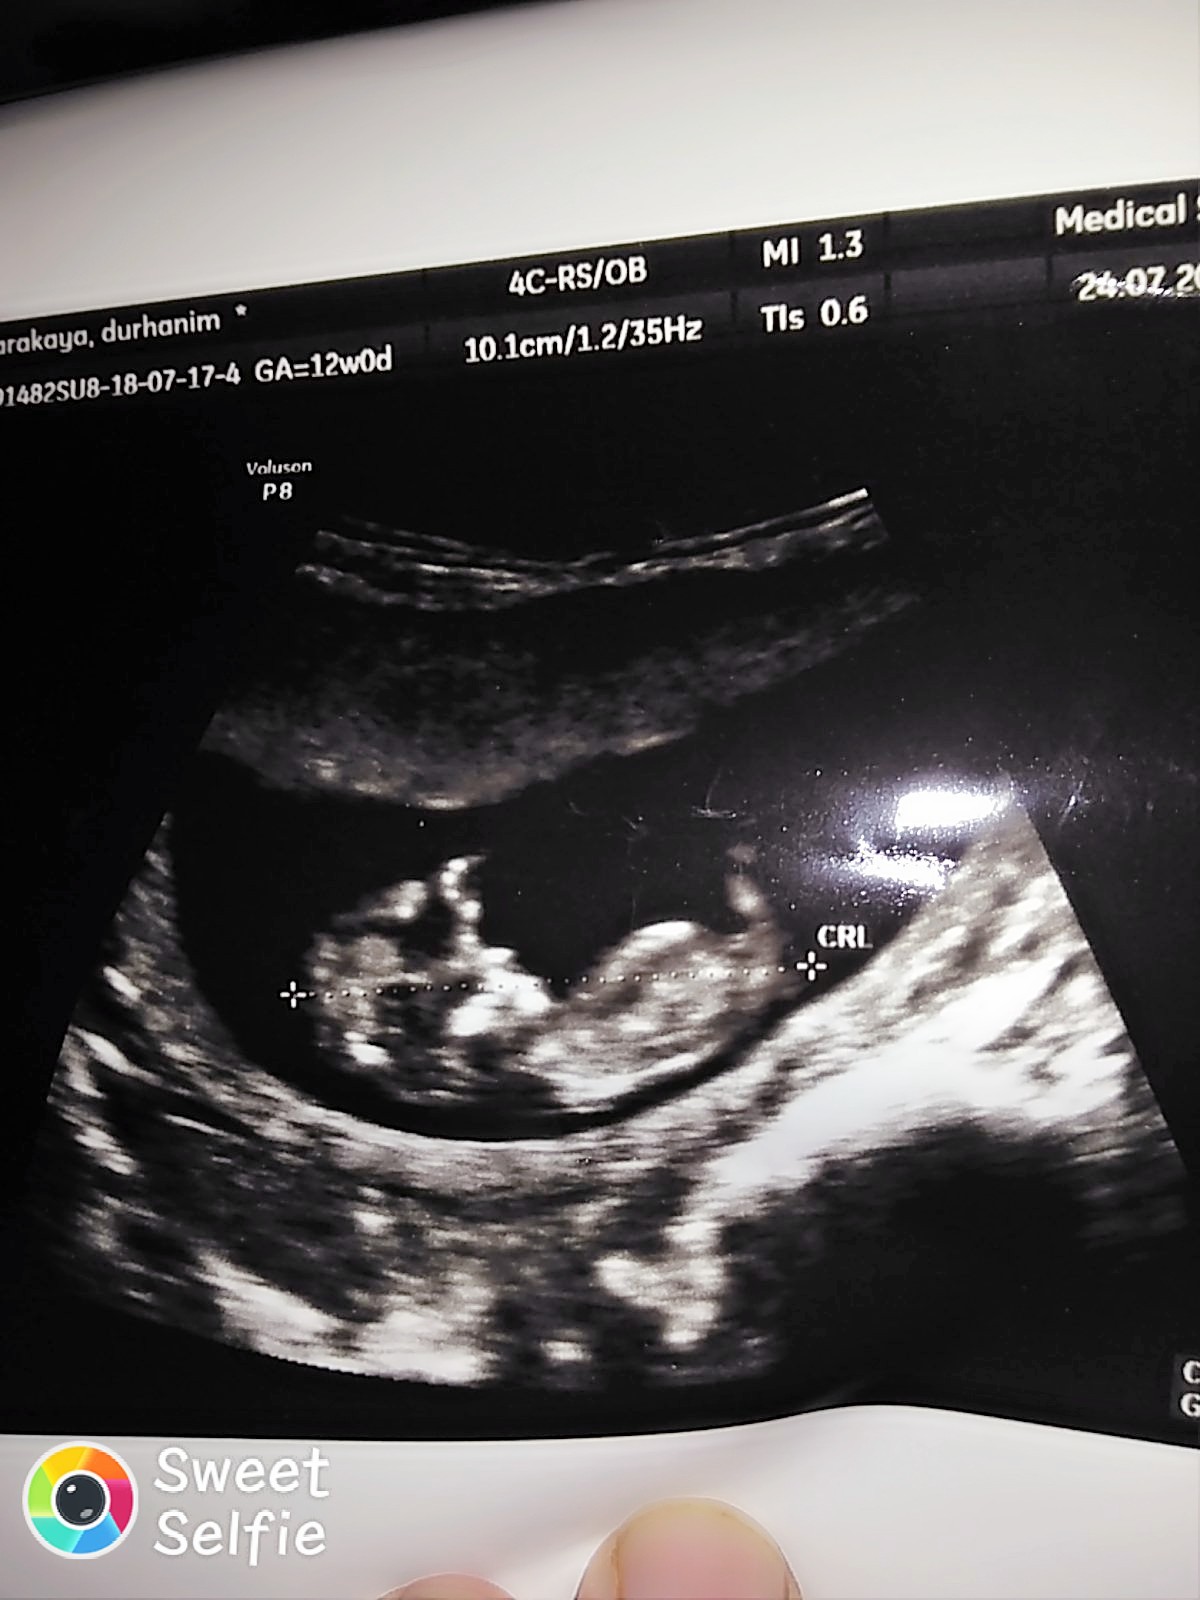

Merhaba ,

Nub teorisiyle cinsiyeti uzman hekimler belirleyebiliyormuş. Bu yüzden doğruluk payı var.

Nub teorisi ile ilgili istatistiki bilgiler şöyledir;

1 hafta sonunda, doğruluk oranı 48 yüzde olduğu

12 hafta sonunda, doğruluk oranı 91 yüzde olduğu

13 hafta sonunda, doğruluk oranı 94 yüzde olduğu